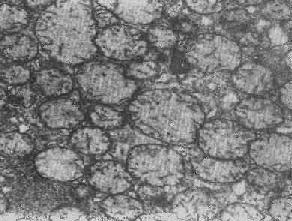

四、线粒体线粒体(mitochondrion)是细胞内主要的能量形成所在,故不论在生理上或病理上都具有十分重要的意义。 线粒体为线状、长杆状、卵圆形或圆形小体,外被双层界膜。外界膜平滑,内界膜则折成长短不等的嵴并附有基粒。内外界膜之间为线粒体的外室,与嵴内隙相连,内界膜内侧为内室(基质室)(图1-8)。在合成甾类激素的内分泌细胞(如肾上腺皮质细胞、卵甾滤泡细胞、睾丸的Leydig细胞等),线粒体嵴呈小管状。内外界膜的通透性不同,外界膜的通透性高,可容许多种物质通过,而内界膜则构成明显的通透屏障,使一些物质如蔗糖和NADH全然不能通过,而其他物质如Na+ 和Ca 2+等也只有借助于主动运输才能通过。线粒体的基质含有电子致密的无结构颗粒(基质颗粒),与二价阳离子如Ca2+及Mg2+具有高度亲和力。基质中进行着β氧化、氧化脱羧、枸橼酸循环以及尿素循环等过程。在线粒体的外界膜内含有单胺氧化酶以及糖和脂质代谢的各种转移酶;在内界膜上则为呼吸链和氧化磷酸化的酶类。 线粒体是对各种损伤最为敏感的细胞器之一。在细胞损伤时最常见的病理改变可概括为线粒体数量、大小和结构的改变: 1.数量的改变 线粒体的平均寿命约为10天。衰亡的线粒体可通过保留的线粒体直接分裂为二予以补充。在病理状态下,线粒体的增生实际上是对慢性非特异性细胞损伤的适应性反应或细胞功能升高的表现。例如心瓣膜病时的心肌线粒体、周围血液循环障碍伴间歇性跛行时的骨骼肌线粒体的呈增生现象。 线粒体数量减少则见于急性细胞损伤时线粒体崩解或自溶的情况下,持续约15分钟。慢性损伤时由于线粒体逐渐增生,故一般不见线粒体减少(甚至反而增多)。此外,线粒体的减少也是细胞未成熟和(或)去分化的表现。 2.大小改变 细胞损伤时最常见的改变为线粒体肿大。根据线粒体的受累部位可分为基质型肿胀和嵴型肿胀二种类型,而以前者为常见。基质型肿胀时线粒体变大变圆,基质变浅、嵴变短变少甚至消失(图1-9)。在极度肿胀时,线粒体可转化为小空泡状结构(图1-10,图1-11)。此型肿胀为细胞水肿的部分改变。光学显微镜下所谓的浊肿细胞中所见的细颗粒即肿大的线粒体。嵴型肿较少见,此时的肿胀局限于嵴内隙,使扁平的嵴变成烧瓶状乃至空泡状,而基质则更显得致密。嵴型肿胀一般为可复性,但当膜的损伤加重时,可经过混合型而过渡为基质型。 线粒体为对损伤极为敏感的细胞器,其肿胀可由多种损伤因子引起,其中最常见的为缺氧;此外,微生物毒素、各种毒物、射线以及渗透压改变等亦可引起。但轻度肿大有时可能为其功能升高的表现,较明显的肿胀则恒为细胞受损的表现。但只要损伤不过重、损伤因子的作用不过长,肿胀仍可恢复。 线粒体的增大有时是器官功能负荷增加引起的适应性肥大,此时线粒体的数量也常增多,例如见于器官肥大时。反之,器官萎缩时,线粒体则缩小、变少。

图1-9 线粒体肿